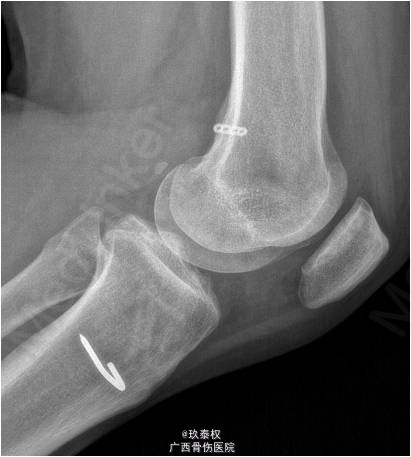

患者女,31岁,因“左膝关节前交叉韧带重建术后半年余,依约返院”入院。患者半年前在我院行“左膝关节镜检,前交叉韧带重建(后外侧束),内侧半月板修补(9针),内侧皱襞切除,门形钉固定术”。现患者依约返院行门型钉拆除术。

查体:双下肢无畸形,左膝关节无静脉曲张、肿胀等,皮温正常,关节间隙压痛,麦氏征(-),蹲走试验(-),过伸试验(-),过屈试验(-),浮髌征(-),髌骨加压研磨试验(-),前抽屉试验(-),后抽屉试验(-),侧方应力试验(-),lachman征(-),关节活动度0-135度,股四头肌无明显萎缩,肌力正常;肢端血运、感觉、活动正常。右下肢及双上肢其余关节未见明显异常。 辅助检查:X线平片及MRI检查未见明显异常。

诊断:1.左膝关节前交叉韧带重建术后;2.左膝关节半月板修补术后。行左膝关节镜检及门型钉拆除术。术后开始行股四头肌肌力训练及踝泵训练,术后第2天开始主动关节屈伸训练,屈膝达90°,术后第3天可完全负重。